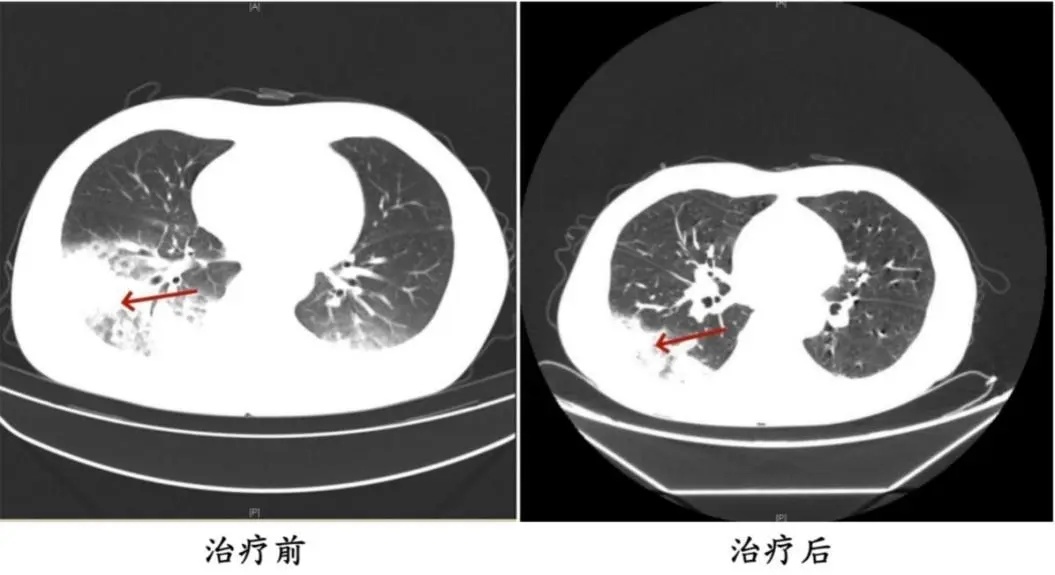

医师问询发现,周先生此前驾车出差,由于气候热,他启动了久未清洗的车载空调,每天在车上的时刻超越十个小时,回来后就呈现了如上症状。经过查看,终究确诊为。军团菌肺炎。

周先生医治前后的肺部CT印象。